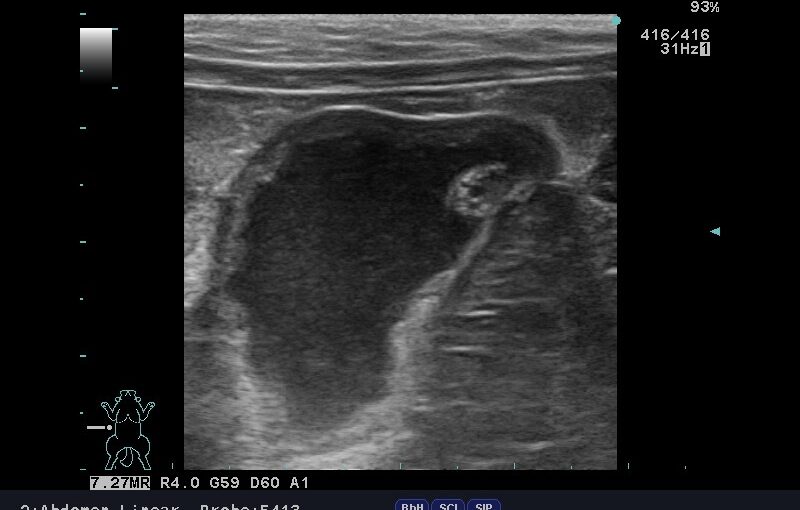

「食滞?」と思ったら…実は妊娠中だったウサギさんの診断例

こんにちは、久我山動物医療センターです。 今回は、少し珍しいウサギさんの症例をご紹介します。 「便が出にくく、食欲もあまりない」とのことで来院された子でしたが、診察を進めていくうちに、私たちも思わず驚く“本 […]